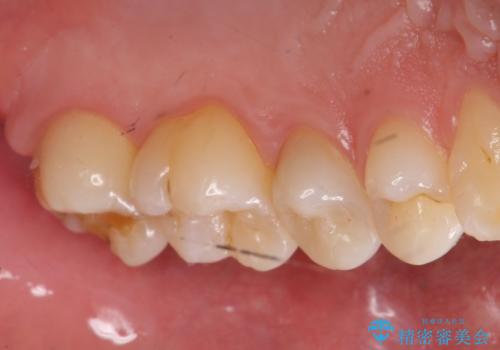

- 上の奥の虫歯をセラミックインレーで修復しました。

奥歯は力がかかるところであるので、保険適応の白い材料は必ず劣化し、2次う蝕(再度虫歯)になる可能性が非常に高いですので全くおすすめできません。

治療前後の写真をお見せして説明したところ、非常に喜んでいただきました。

- emaxインレー:7万円費用は治療当時の料金となります

特に自費のインレーの適合(歯にぴったり合っている)はとても良く、虫歯になりにくいです。